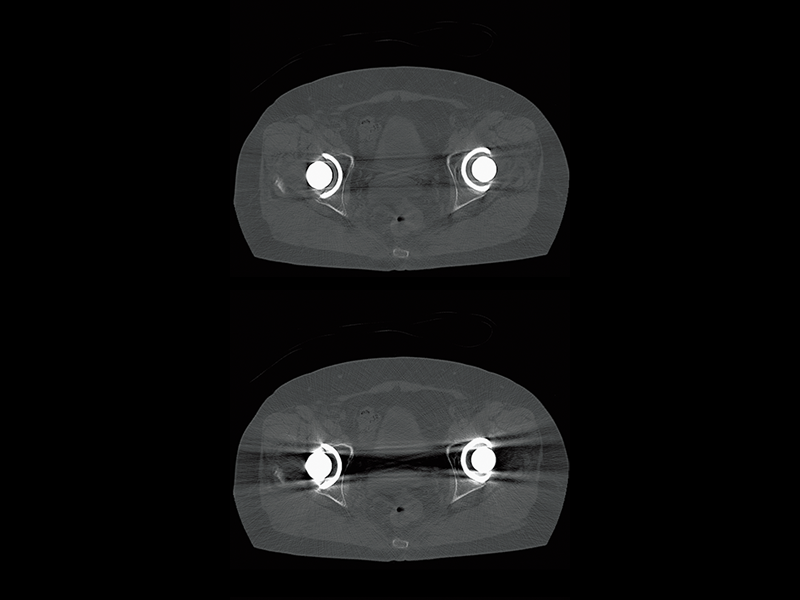

Hip joint(HiMAR Plus)